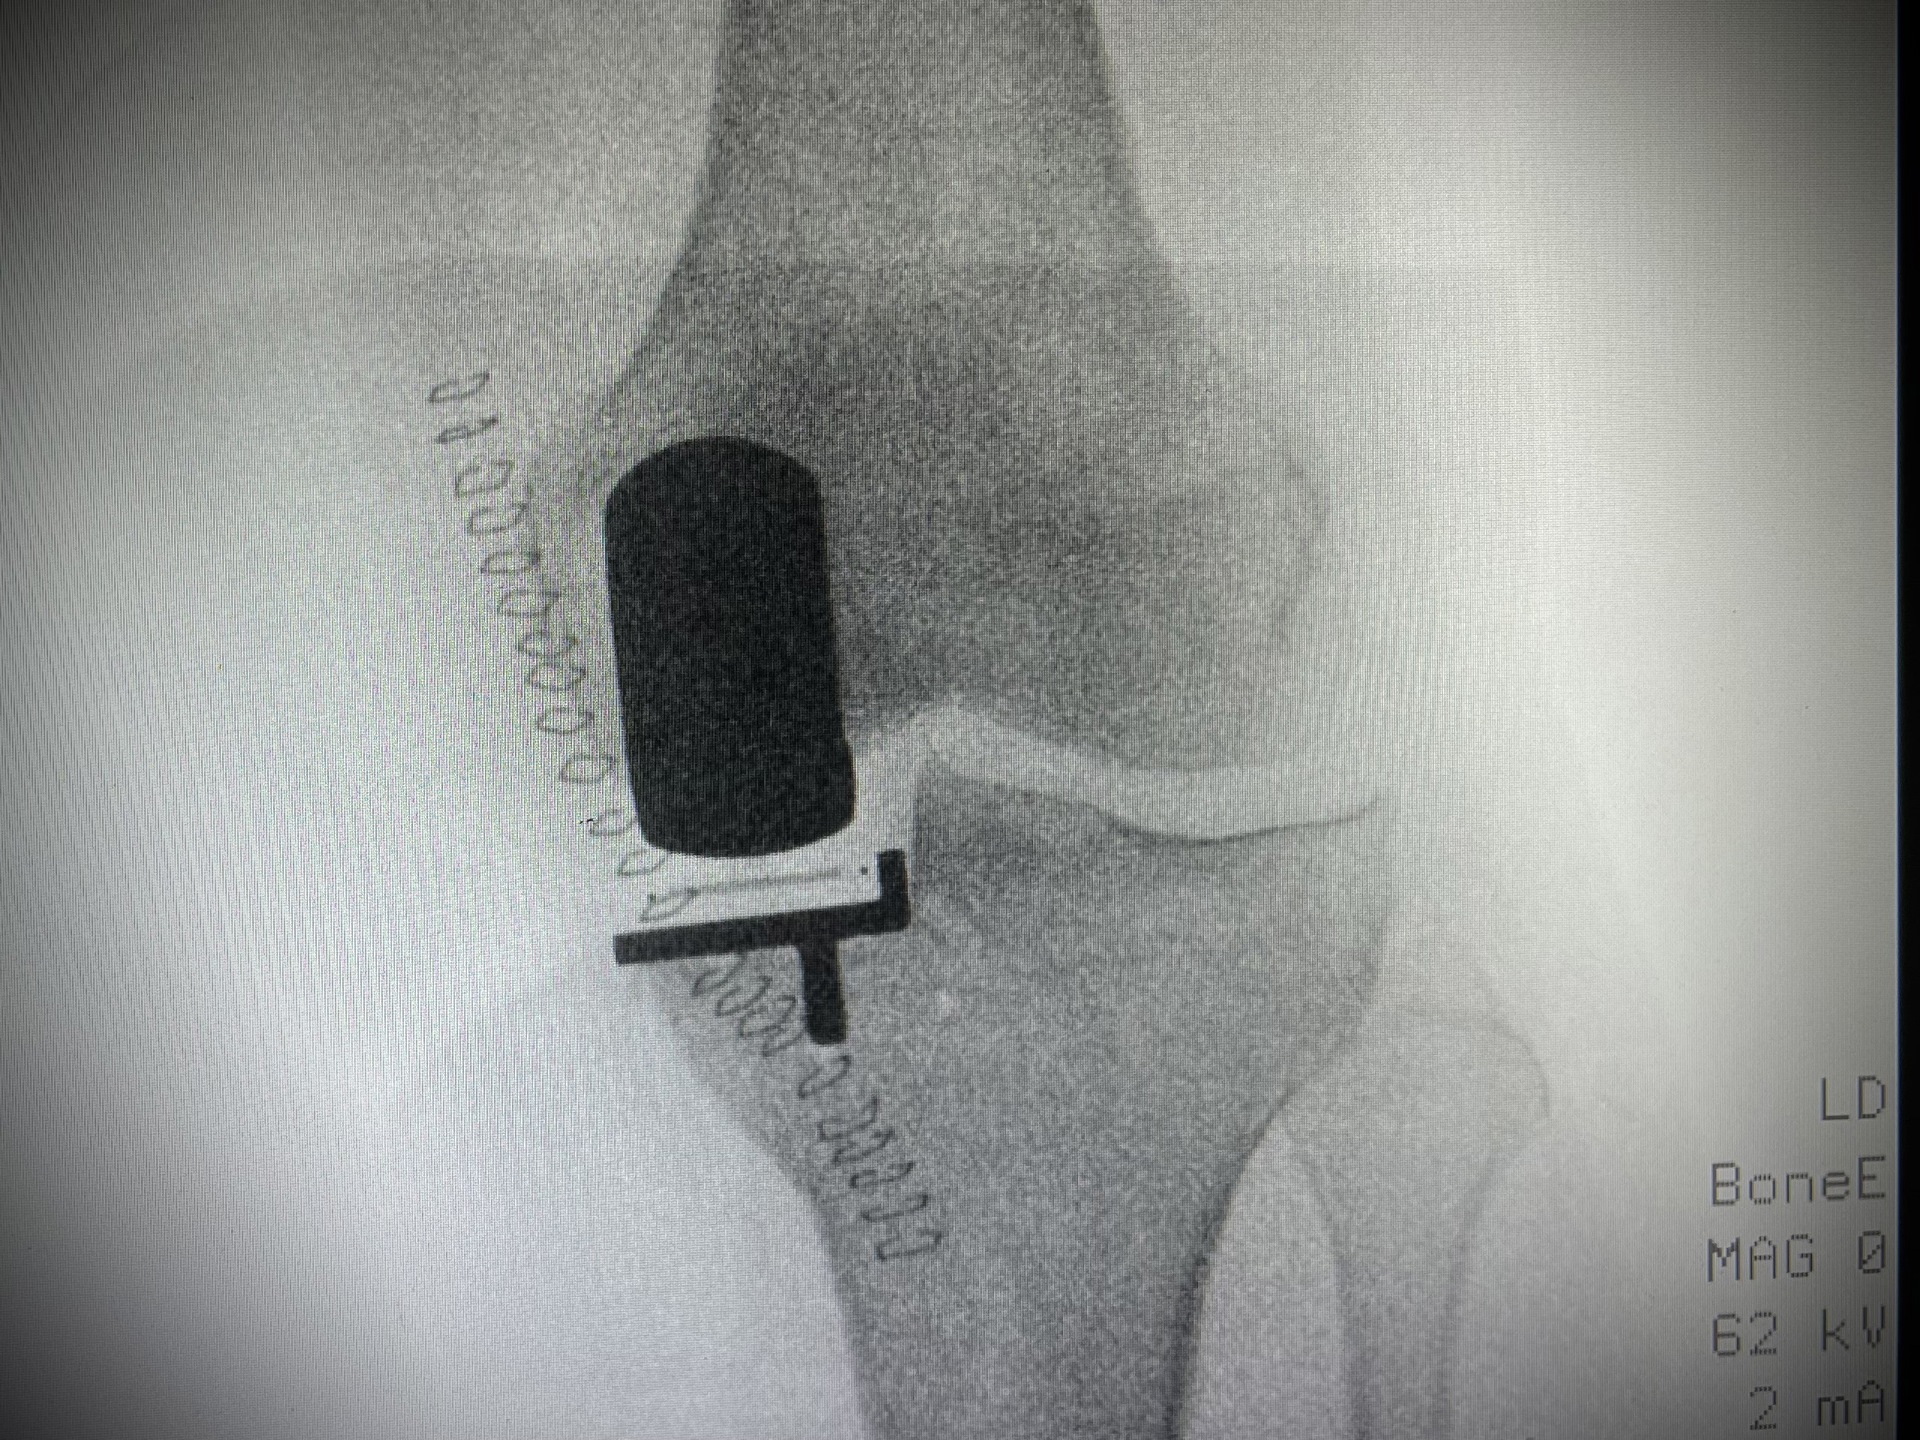

• Endoprothetik des Hüft- und Kniegelenkes

• Zertifizierter Hauptoperateur des Endoprothetikzentrums der Asklepios Klink Lich